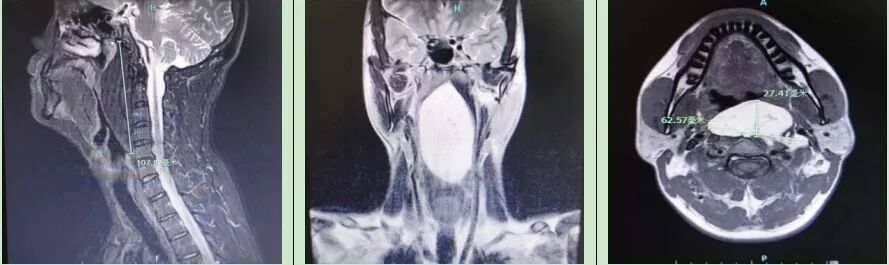

入院后耳鼻咽喉科咽喉头颈组团队立即为其安排详细的术前检查。电子鼻咽喉镜结果提示自鼻咽后壁至下咽后壁约双侧披裂平面见黏膜下巨大光滑隆起,肿物向前膨隆,遮挡部分喉口,口咽及下咽腔前后径狭窄。颈部核磁提示咽后间隙-左侧颈动脉间隙脂肪瘤。综合上述检查结果,初步考虑患者为“咽后间隙-颈动脉间隙巨大脂肪瘤”,手术切除是首选治疗方案。

为了制定最佳的麻醉及手术治疗方案,耳鼻咽喉科刘卫卫主任组织咽喉头颈组组长代保强主任、马金华副主任、麻醉科孙文波主任、瞿敏副主任等进行了详细的术前讨论,专家们一致认为:1.患者咽腔狭窄,肿物遮挡部分喉口,麻醉插管有难度,必要时需先行气管切开;2.患者肿物巨大(上下径长约11cm),肿瘤下缘达第5颈椎近食道入口平面,经口咽后壁入路无法直视下完整暴露肿物上下缘,故应采取经口内镜辅助下的手术方式,并联合等离子系统以减少术中出血,若无法完整切除,应做好动力系统辅助下囊内切除的准备;3. 患者口咽部创面较大,术后形成血肿风险高,术中应确切止血,放置引流,必要时行气管切开保护气道。

6月21日,麻醉科瞿敏副主任为患者实施全身麻醉,麻醉时见口咽部后壁隆起较为明显,声门暴露有一定困难,经耐心调整插管角度后,顺利完成经口气管插管。手术由代保强主任主刀,裴达主治医师、耿珊珊主治医师配合。首先使用开口器暴露口咽部,见肿瘤向咽腔膨隆,取咽后壁正中纵行切口,长约5cm,切开咽部黏膜后暴露肿物,见肿物有被膜,探查后发现其背面及侧缘与椎前颈长肌粘连较重。于0°及70°内镜辅助下沿肿瘤被膜钝性分离并联合应用低温等离子刀分离并切断肿物背膜与椎前肌肉的粘连带,完整切除肿物。见肿物呈淡黄色分叶状,表面光滑,大小约11.0cm×5.5cm×3.0cm,检查术腔无肿物残留,无活动性出血点,放置引流管1枚,逐层对位缝合咽后壁肌肉及黏膜。术后病理证实为纤维脂肪瘤。